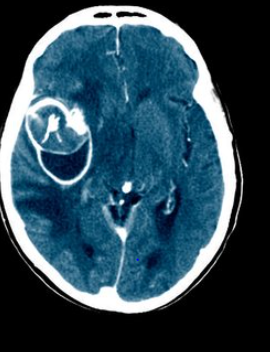

뇌출혈이 의심되는 경우, 즉시 의료 기관을 방문하여 정밀 진단을 받는 것이 중요합니다. 컴퓨터 단층촬영(CT)이나 자기공명영상(MRI) 검사를 통해 뇌 내부의 출혈 여부를 확인할 수 있으며, 필요한 경우 적절한 치료를 받을 수 있습니다.